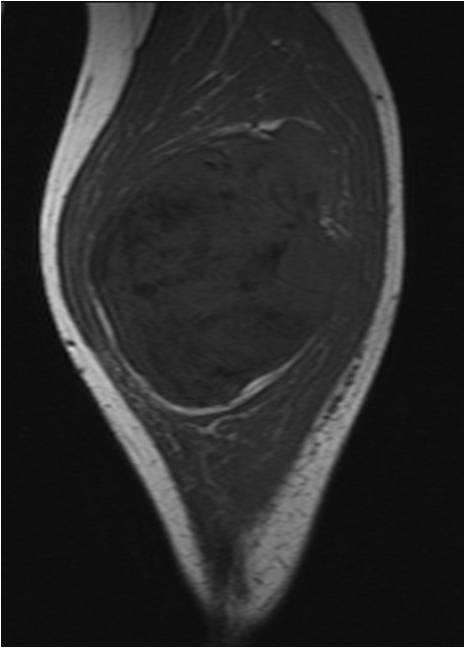

On radiographs, Low Grade Fibromyxoid Sarcoma presents as a discrete mass with soft tissue density without mineralization. MRI shows a well circumscribed heterogeneous mass, primarily hypo or isointense to muscles on T1-weighted image. The majority of tumors demonstrate heterogeneous signal intensity on T2-weighted images, correlating with the histological characteristics of low grade fibromyxoid sarcoma. Although 48 % of the patients demonstrate hyperintense signal and the rest of patients present admixed of hypo and Isointense signals (Fig. 1-5).

Fig. 1 & 2: MRI Axial (Fig. 1) and Coronal T1-weighted MR image (A) of a Low Grade Fibromyxoid Sarcoma demonstrates a well-defined mass of intermediate signal intensity with muscle and central areas of hypo intensity in the posterior compartment of the calf.